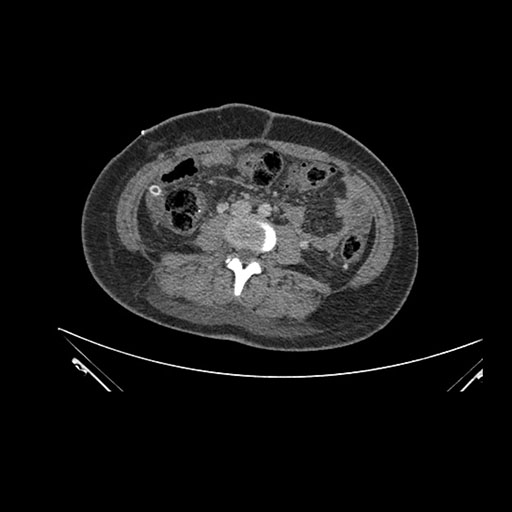

Axial Arterial

Axial Venous